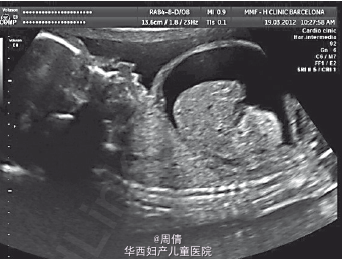

超声提示胎儿颈部冠状位正常的喉部和声带闭锁 胎儿颈部冠状位正常的喉部和声带图像 胎儿颈部冠状位正常的喉部和声带闭锁的图像

诊断为先天性高气道阻塞综合征 行胎儿镜治疗 肉眼观喉部闭锁在声带水平的横切面,有增厚和发育异常 下方可见纤维组织和融合的声带